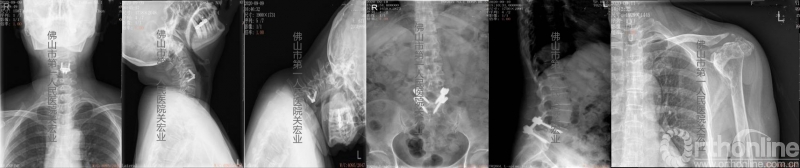

术前放射检查

影像学术前、术后对比

A:术后颈后、枕部向头顶的放射痛明显缓解。左上肢肌力提高一级,双侧下肢本体感觉改善。术前寰枢椎旋转脱位、下颌偏歪、齿状突上移、脊髓向右侧偏移的情况,术后影像学可见均有明显改善。